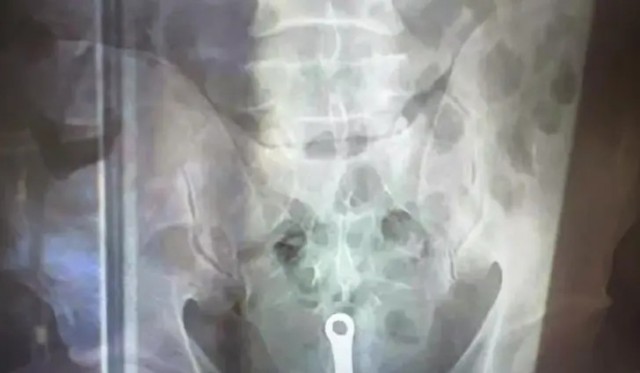

Уфимец вызвал скорую помощь по необычному поводу – в его заднем проходе застрял туалетный ершик

Сообщается, что мужчина позвонил в скорую помощь с жалобами на боль и неприятные ощущения. Сотрудники скорой помощи лишь прибыв по вызову обнаружили причину этого вызова – в заднем проходе мужчины застрял инородный предмет в виде туалетного ершика. Как он туда попал, пациент объяснить врачам не смог.

Пациент был госпитализирован в больницу, где ему сделали рентген, после чего удалили посторонний предмет из тела мужчины. После этого пациент был отпущен домой.